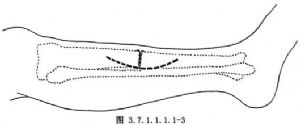

以脛骨不癒合處爲中心,用弧行或縱行切口顯露骨斷端(圖3.7.1.1.1.1-3)。切開兩側骨端骨膜,但不要廣泛剝離,一般以不超過脛骨周徑的一半爲宜。注意保護周圍軟組織和骨膜的血管。